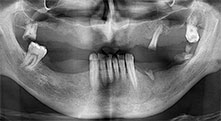

Pourriez-vous décrire brièvement par exemple comment vous procédez pour mobiliser les blocs osseux en vue d’une greffe ?

Pr Bratu : Nous préférons prélever l'os sur la crête oblique externe de la mandibule postérieure, et non dans la région interforaminale. Après l'incision des tissus mous, nous utilisons les nouvelles scies pour définir la quantité d'os à prélever. De la même manière, nous les utilisons également pour la totalité de la préparation dans presque 80 % des cas. Nous avons également parfois recours à d'autres instruments piézoélectriques et, pour terminer, à un burin pour mobiliser le bloc. Nous trouvons cette technique chirurgicale très efficace.